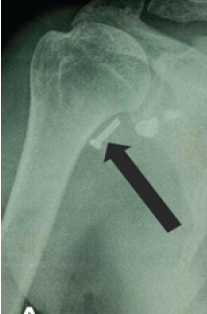

Rare Presentation of Chronic Anterior Instability with Concomitant Triad of Anterior Labral Periosteal Sleeve Avulsion, Hill–Sachs, and Humeral Avulsion of the Glenohumeral Ligament Lesions: A Case Report

Hady Ezzeddine , Rita Saad , Wendy Ghanem , Mohamad Badra , Ramzi Moucharafieh , Ziad Noun